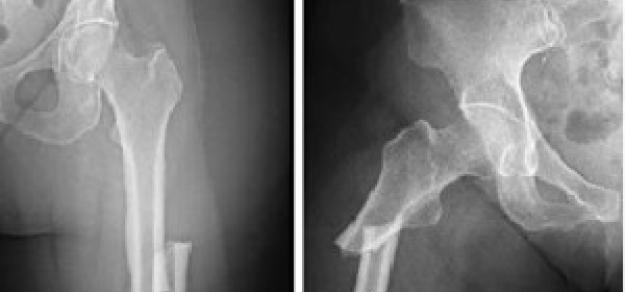

Combinaciones de implantes de elección en reemplazo total de cadera

BMJ, 2 de noviembre de 2017 Las combinaciones de implantes más recientes no fueron mejores que la combinación de implantes de referencia en términos de riesgo de cirugía de revisión o la puntuación Harris de cadera.